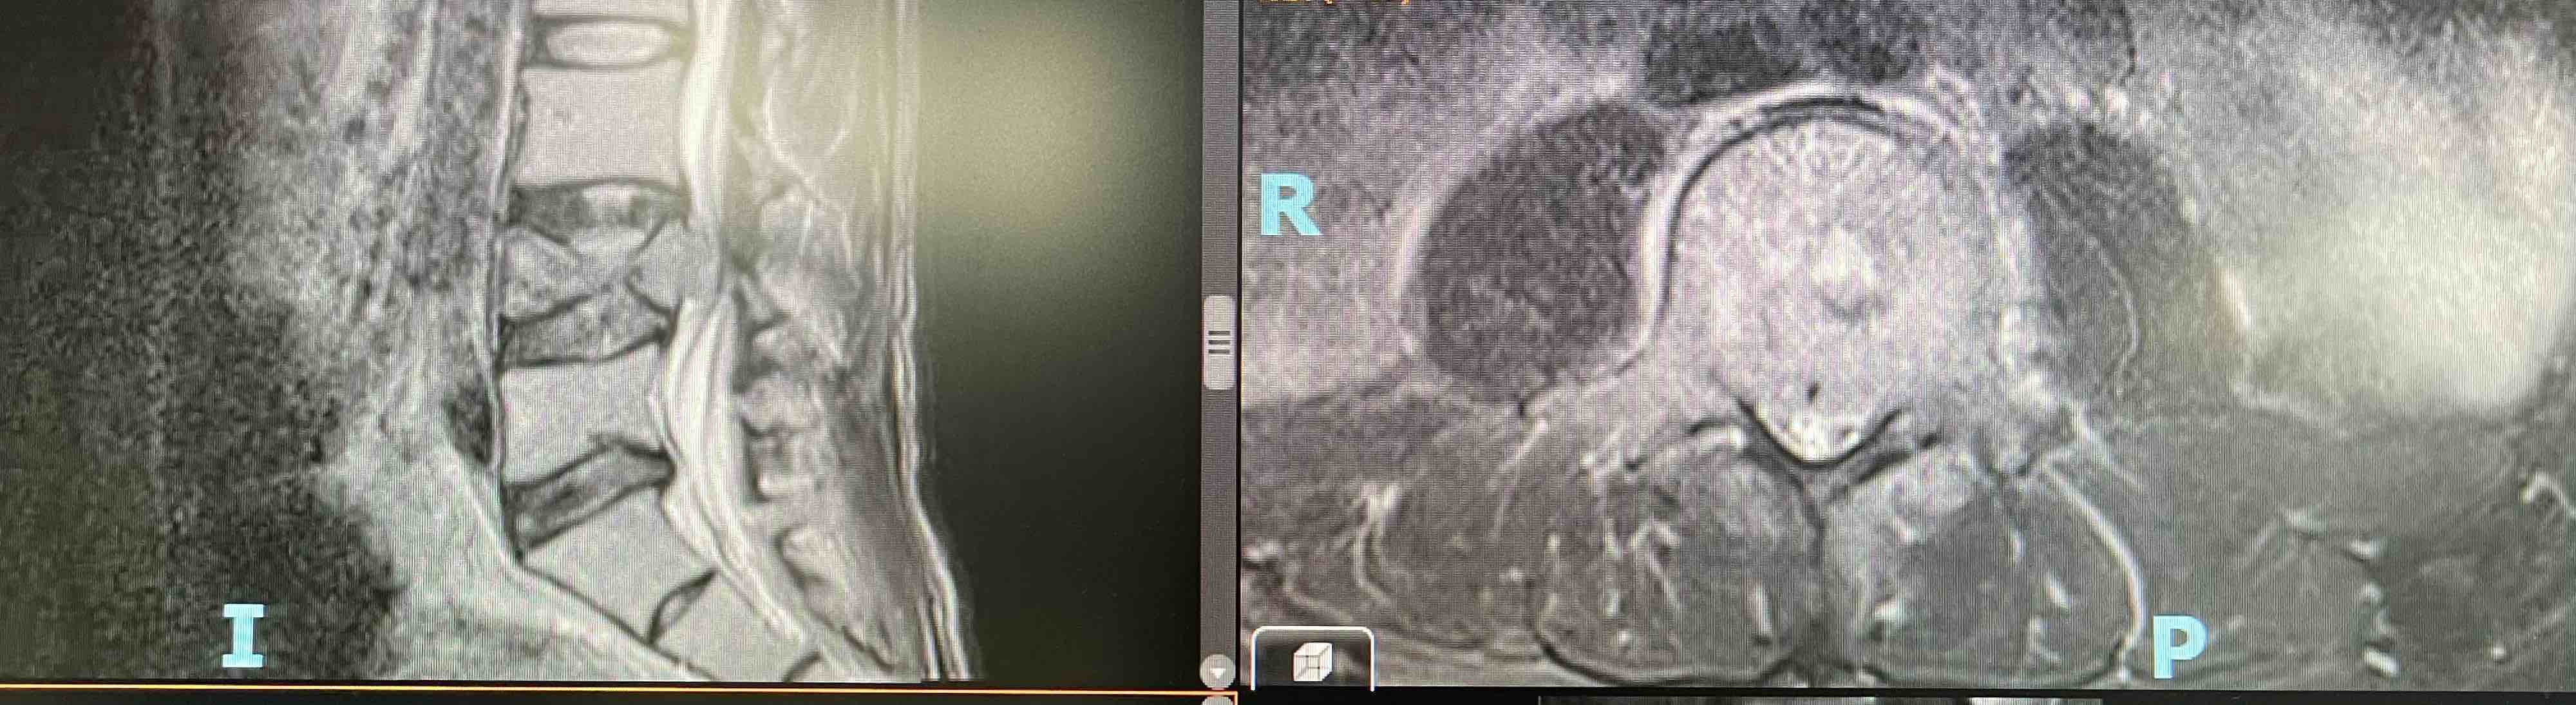

患者中年男性,消化道恶性肿瘤术后5年,胸腰椎转移。患者就诊主要症状:胸腰背部疼痛、腰骶交界区为重,夜间明显,弯腰受限,双侧小腿外侧麻木;体查:T10-11、L4-S1节段压痛、叩痛阳性,疼痛可放射至右侧小腿及足背,双侧L5以下感觉平面减退,右侧小腿及踝关节拮抗肌肌力IV级,余未及异常。

影像学检查如下: